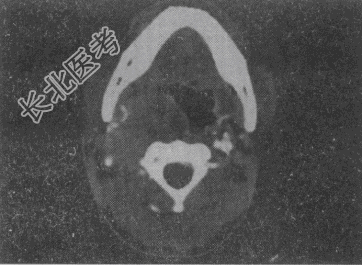

- 单项选择题男,41岁, 右侧咽部不适2年余,有异物感, 声音嘶哑,CT如图, 最可能的诊断是

A、颈动脉体瘤

B、咽旁转移瘤

C、咽旁淋巴瘤

D、小唾液腺瘤

E、咽旁神经鞘膜瘤